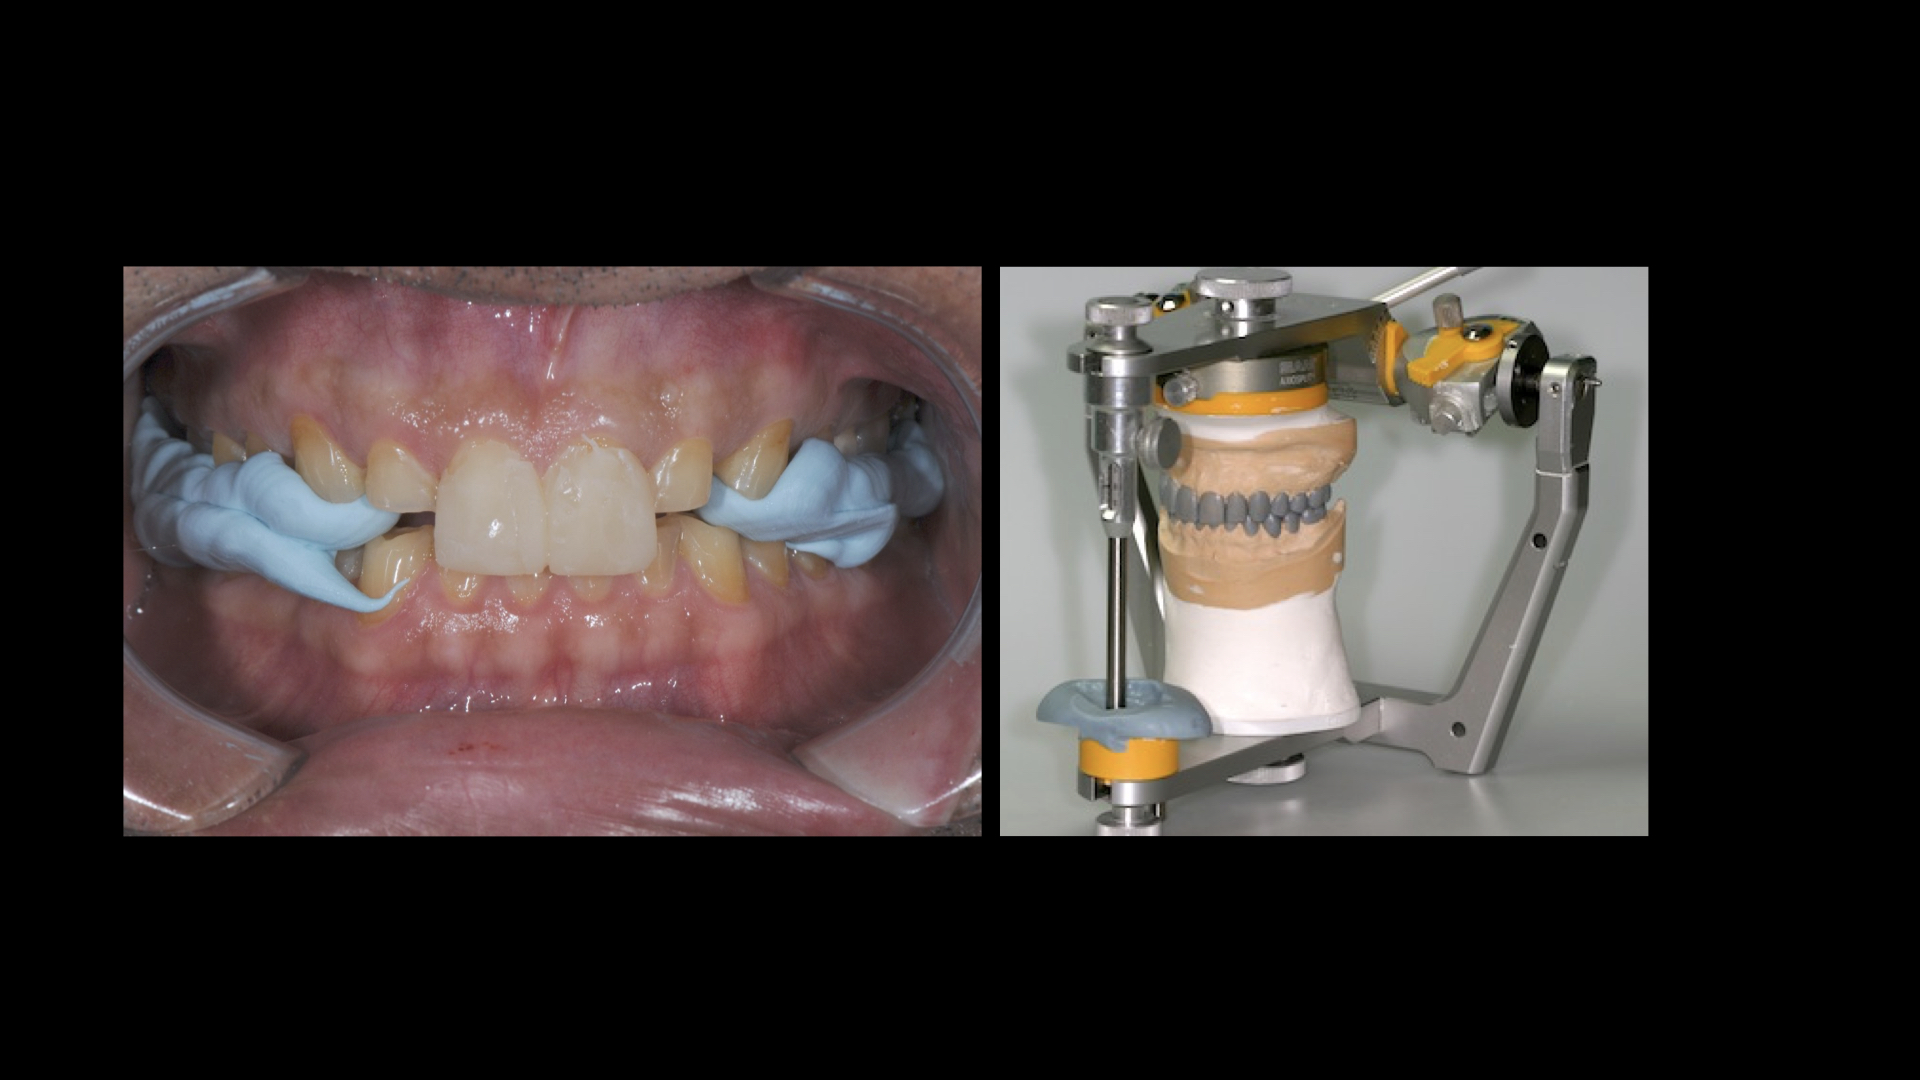

A Day of Occlusion - Updated Program !

This full, 1-Day (7 hour) lecture and demonstration program was presented by Dr Michael Mandikos in November 2025. It has …

Understanding Occlusion and Splints

This is a recording of the full, 1-Day lecture and demonstration program as presented by Dr Michael Mandikos. The course …